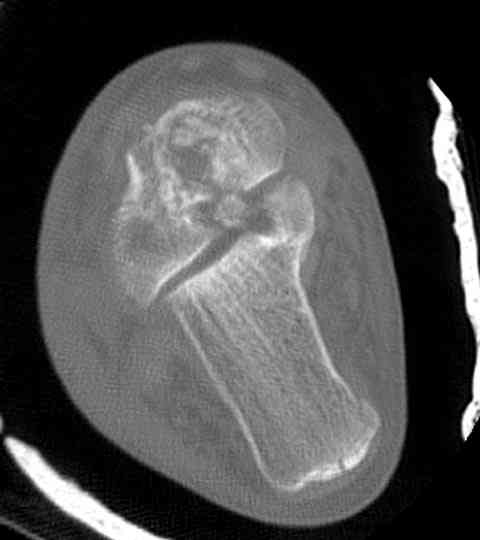

Для оценки состояния нужны дополнительные исследования, например

> Canale или Broden ренгенограммы

повторили рентгенограммы и доделали проекции, к единому мнению все еще не пришли

На ренгенограмме не уловил многоскольчатость тарана, чтобы доказать, конечно, можно было исследовать на КТ, потом КТ дает ориентацию фрагментов.